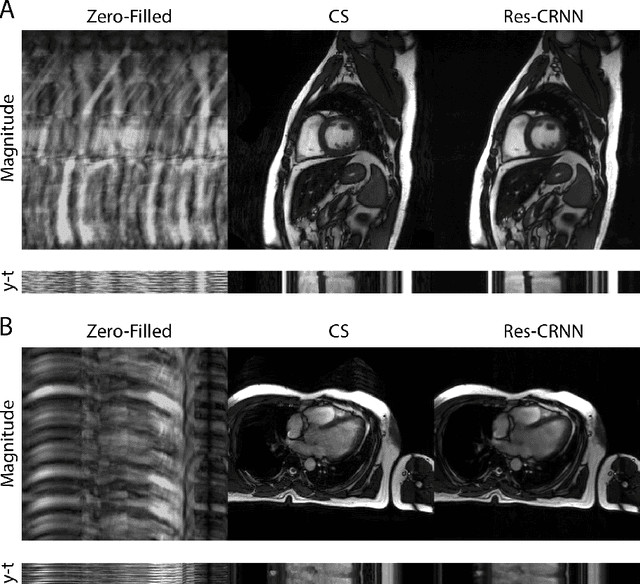

Abstract:Real-time cardiac cine MRI does not require ECG gating in the data acquisition and is more useful for patients who can not hold their breaths or have abnormal heart rhythms. However, to achieve fast image acquisition, real-time cine commonly acquires highly undersampled data, which imposes a significant challenge for MRI image reconstruction. We propose a residual convolutional RNN for real-time cardiac cine reconstruction. To the best of our knowledge, this is the first work applying deep learning approach to Cartesian real-time cardiac cine reconstruction. Based on the evaluation from radiologists, our deep learning model shows superior performance than compressed sensing.